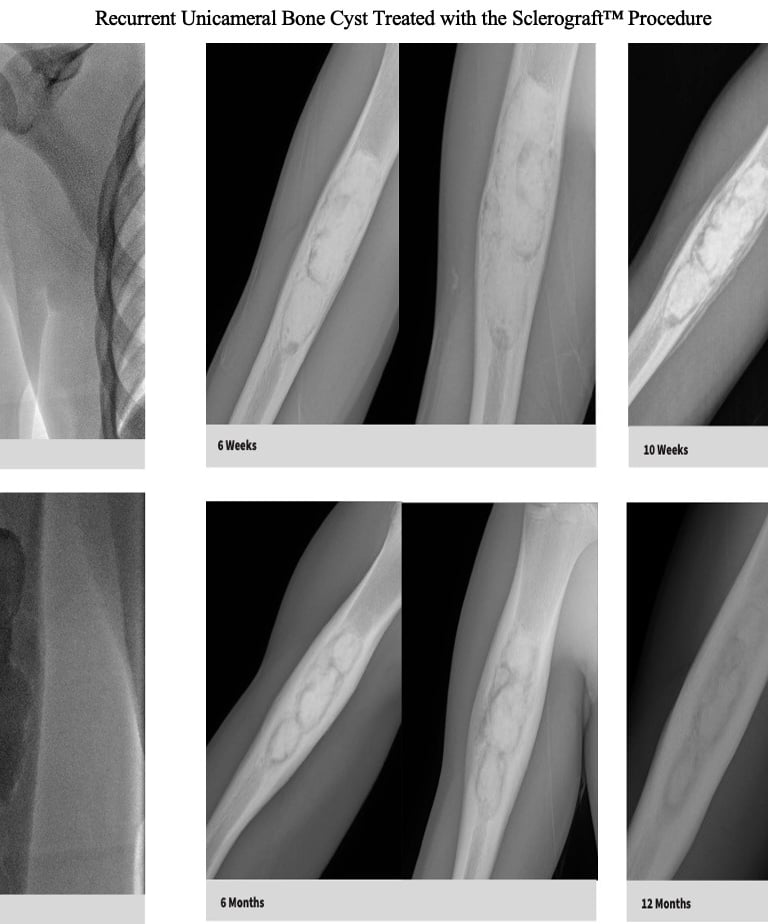

Quick recovery and bone formation seen between 6 weeks to 3 months

Follow-up imaging is usually obtained at 6 weeks, 3 months, 6 months, 12 months and annually for at least 3 years.

The long term follow-up with x-rays is critical because of the possibility of bone cyst recurrence. Generally, if a recurrence occurs, it tends to be noticeable by the 6 month mark

Gallery

Explore our educational resources and images